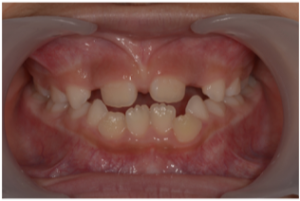

ちなみに受け口な7歳の女の子は現在プレオルソと部分矯正でここまで改善しています☺️

治療前

現在

上の前歯2本がだいぶ前方に誘導されているのが分かると思います。

この子は低位舌といい、舌で下の前歯を押すような位置に舌をいつも置いています。プレオルソとあいうべ体操で舌のポジションも改善中です✨